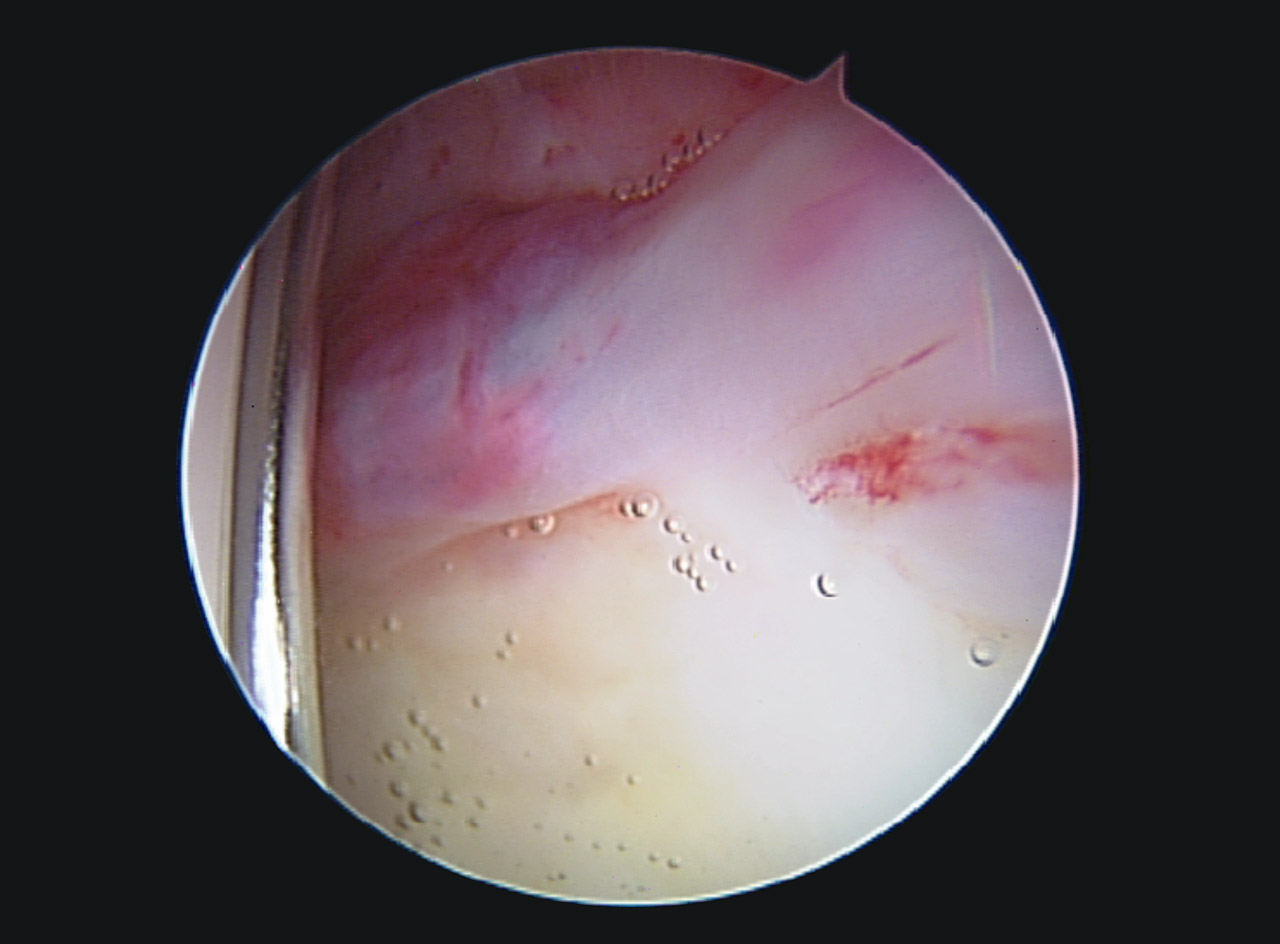

En la exploración artroscópica se observó un labrum hiperémico en la región anteroexterna, con un aumento del tejido sinovial adyacente al labrum. Se realizó una destrucción de dicho tejido mediante el uso de un vaporizador de radiofrecuencia, tal y como se observa en las Figuras 3 y 4. El complejo condrolabral se encontraba conservado y no requirió reanclaje.